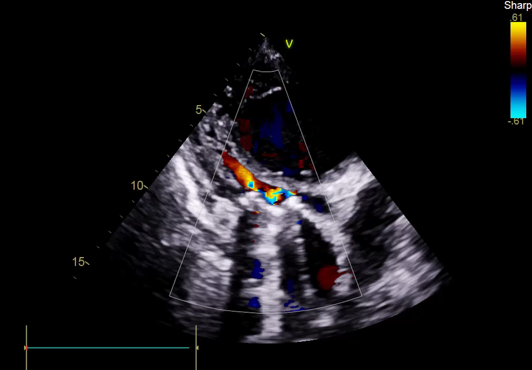

TEE, TEE and Floro showed both the leaflets to be stuck, almostno flow across the PV. The RV was higely dilated and there was severe RVdysfunction

Since TLT was not possible and surgeon refused for emergencyTranscatheter valve disruption was planned. The issues involve in the procedure were 1.Septal Puncture -due to pericardial patch in IAS, alteredanatomy due to Sx & ac dilatation of LA- Angle of puncture and Site ofpuncture. 2 Selection of wire3.Balloon- Size, make ( Compliant Vs NC), 4.Complication-like disc embolization, stuck disc leading to ac severe MA and strud fracture. The septa puncture was done as standard approach, a V18 wirewas parked in PV through a 7f Mullin sheath, Straight Turmo wire was was takenthrough a 6 JR to cross the valve and a 6 x 40 Armada balloon was dilatedacross the disc. Good acute result was obtained. The LA mean decreased from36-40 to 10-12mmHg. Post procedure the inotropic support, O2 demand decreasedover next 12 hr. However after 24 hr pt developed refractory RH failure and persistentanuria requiring SLED. And pt succumbed to the procedure 3 days after theprocedure.